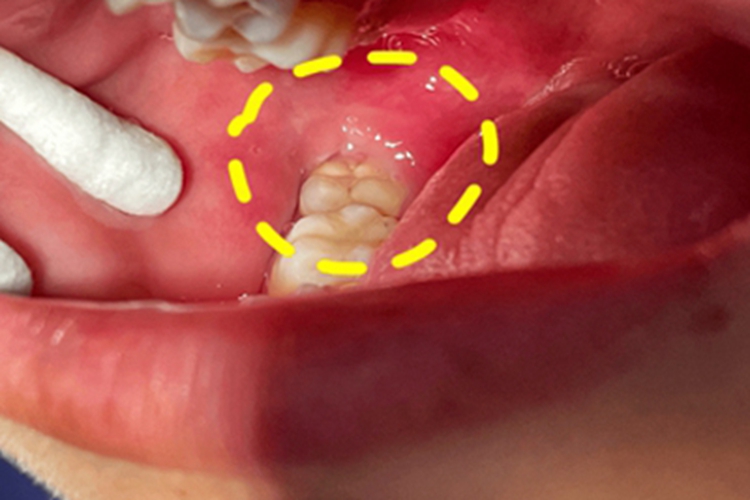

智齿冠周炎发生后,可见患者牙龈出现损害,表现为局部发红、肿胀,甚至糜烂、流脓等。患者自觉疼痛,吞咽、进食时加重,甚至张口受限。

智齿冠周炎主要与口腔卫生差等因素有关。临床上智齿在萌出过程中形成与口腔相通的盲袋,盲袋内易存储食物残渣、唾液、细菌,在适宜的口腔温度和湿度环境中很容易滋生细菌,容易引发冠周智齿炎。